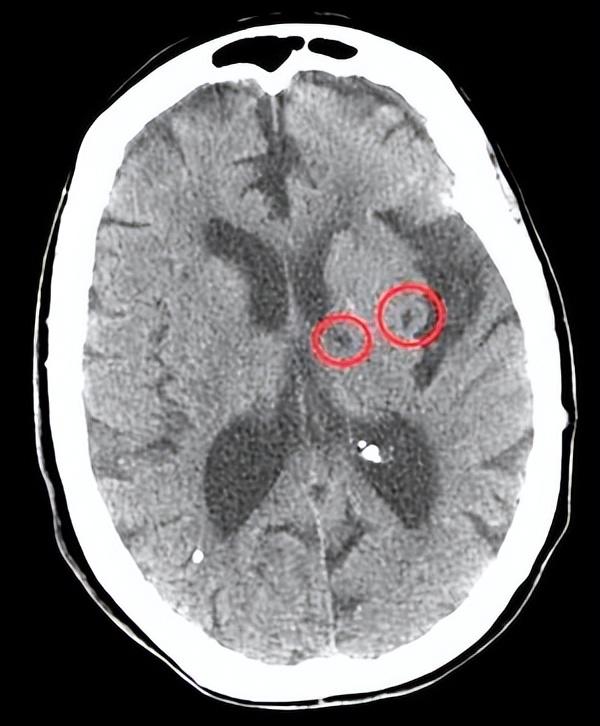

60岁的王阿姨在一次例行体检中被发现有“腔梗”,但她平时并没有任何不适症状。这种情况并非个例,事实上,无症状腔隙性脑梗死(简称无症状腔梗)在中老年人群中相当常见,却常常被忽视。

那么,如何诊断无症状腔梗呢?一般来说,直径在3mm以下的病灶为微梗死,3-15mm的病灶为腔隙性脑梗死。主要通过CT或MRI进行诊断,其中MRI的敏感性和精确性均优于CT。诊断标准包括:CT和/或MRI发现脑内有梗死灶或软化灶;未见相应的临床表现;排除其他非血管性疾病以及脑出血引起的软化灶;如果DWI显示为明显高信号者,则为新发梗死灶;没有脑梗死或短暂性脑缺血发作病史。